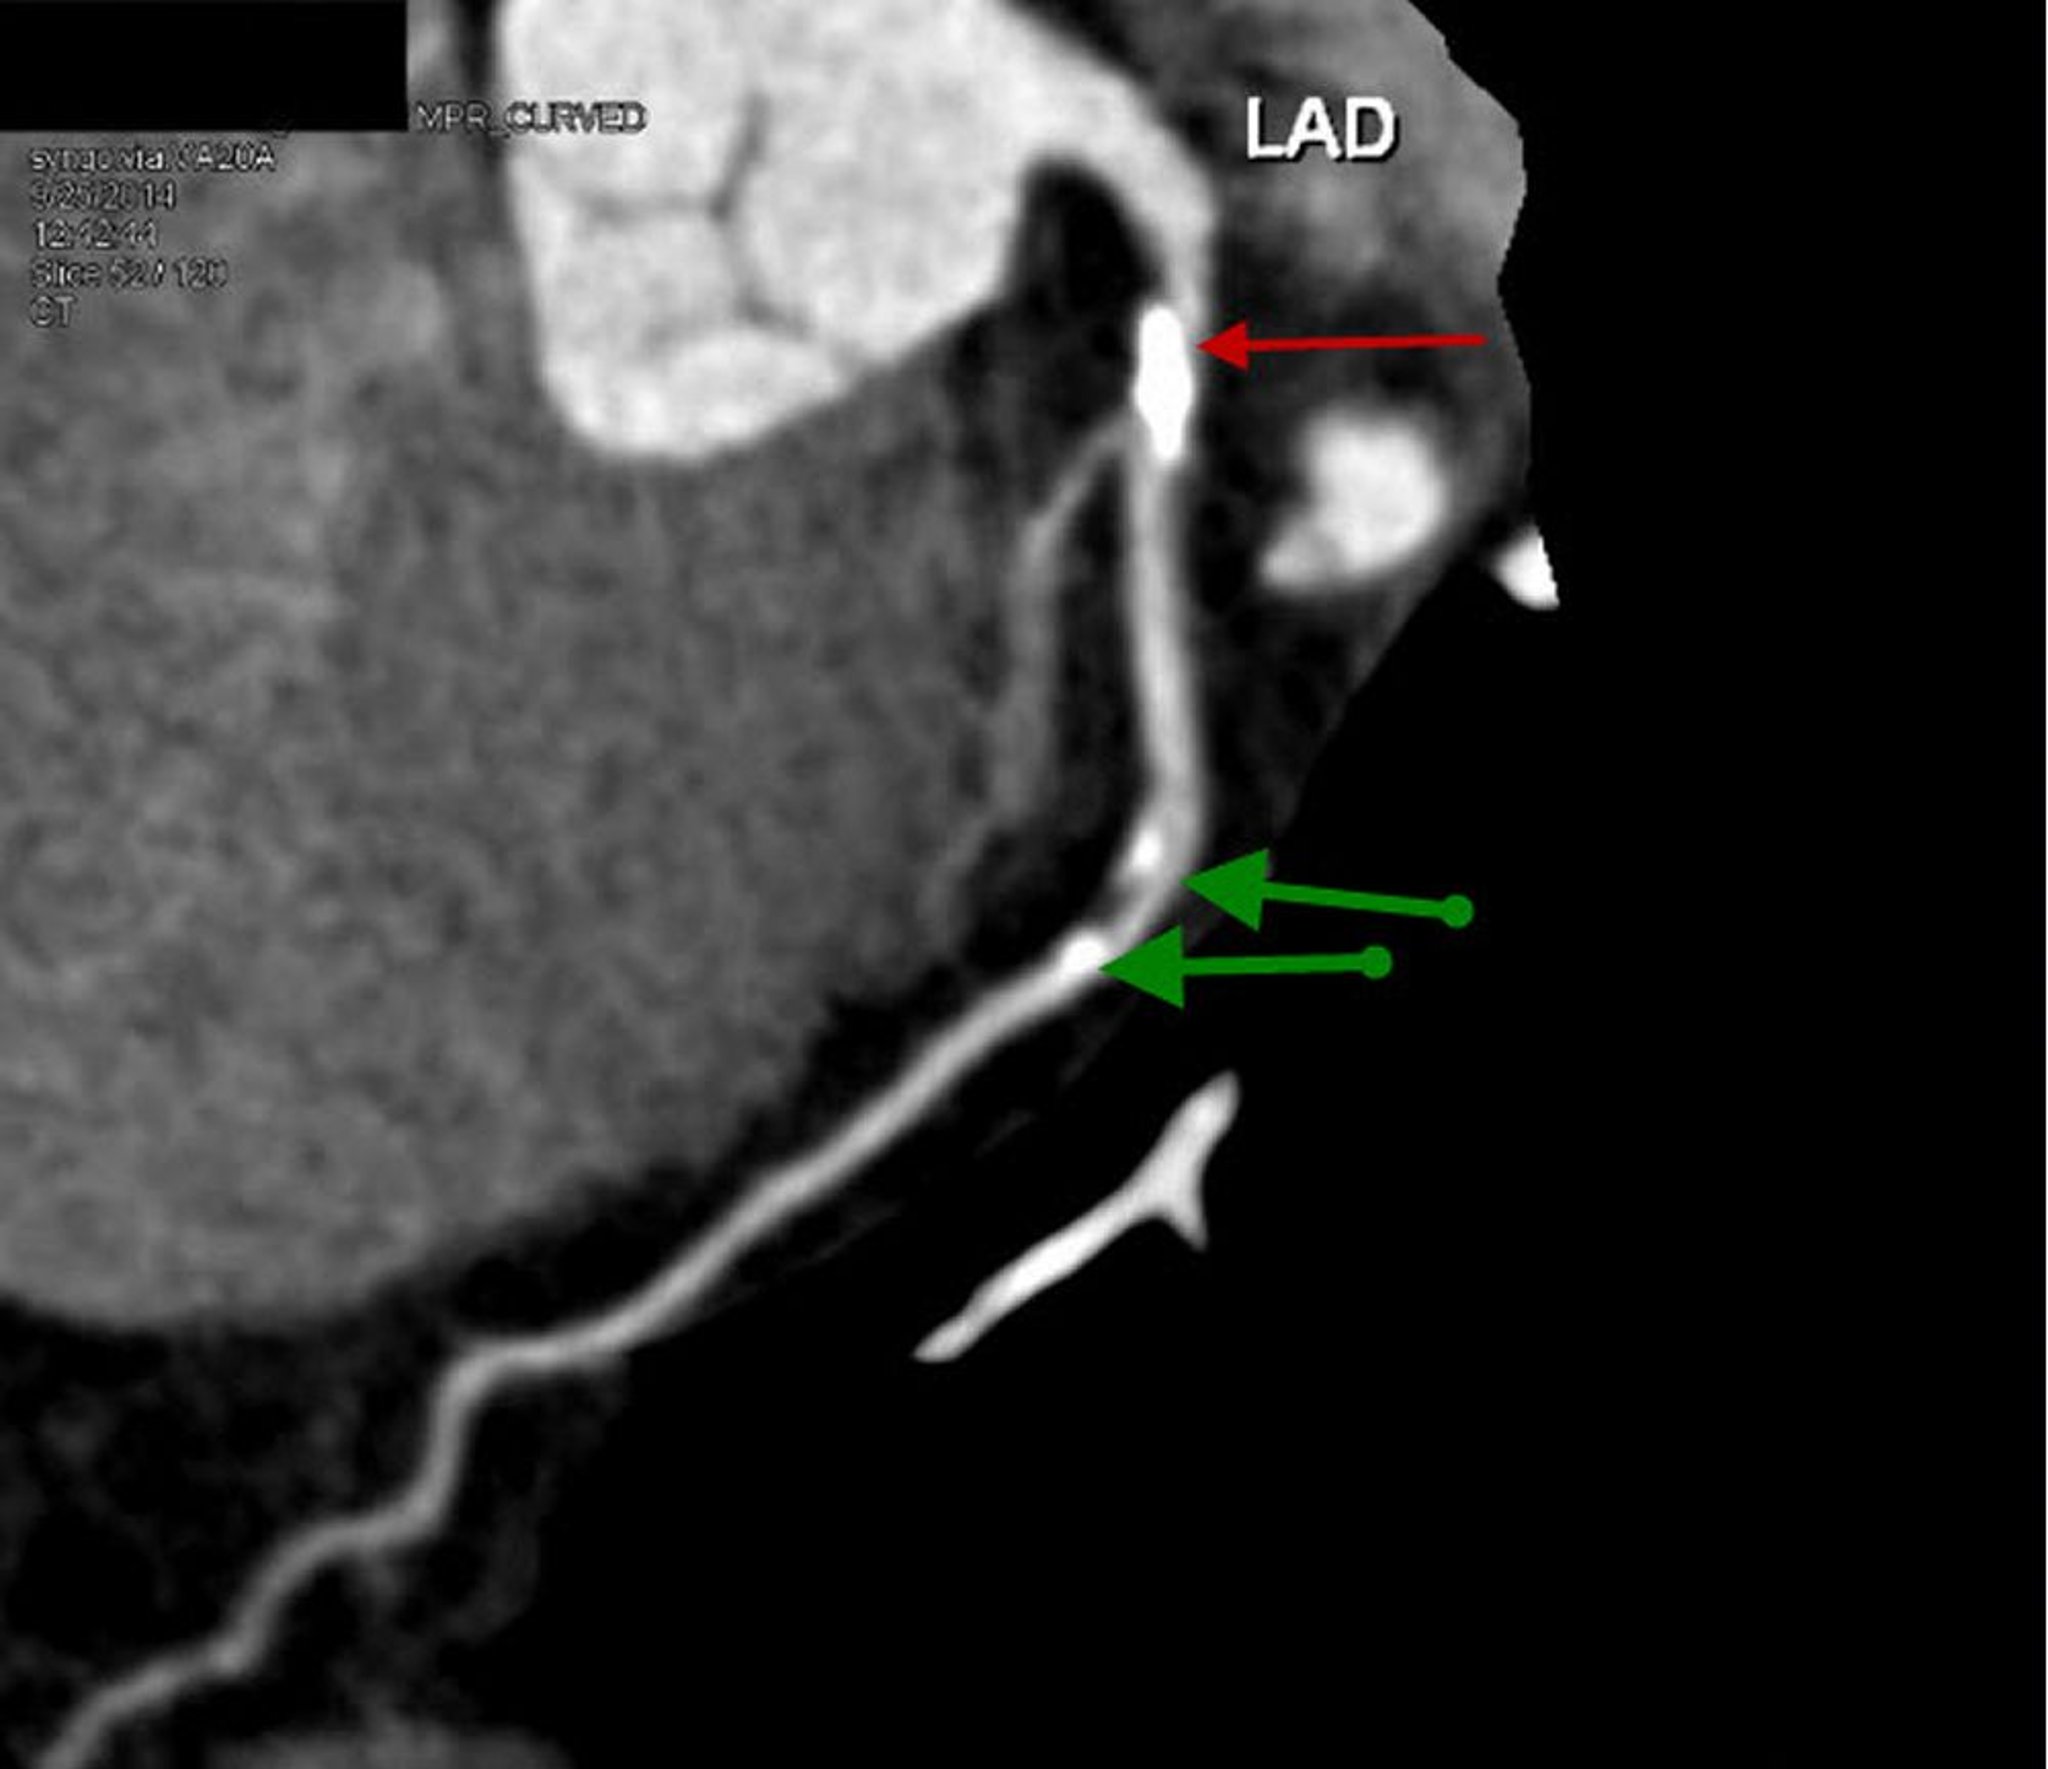

この造影CT画像は,著明な石灰化プラークおよび70%の狭窄(赤矢印)を伴う左前下行枝近位部の再構成された矢状断像である。中間部のLADには20~30%の軽度の狭窄が認められる(緑矢印)。